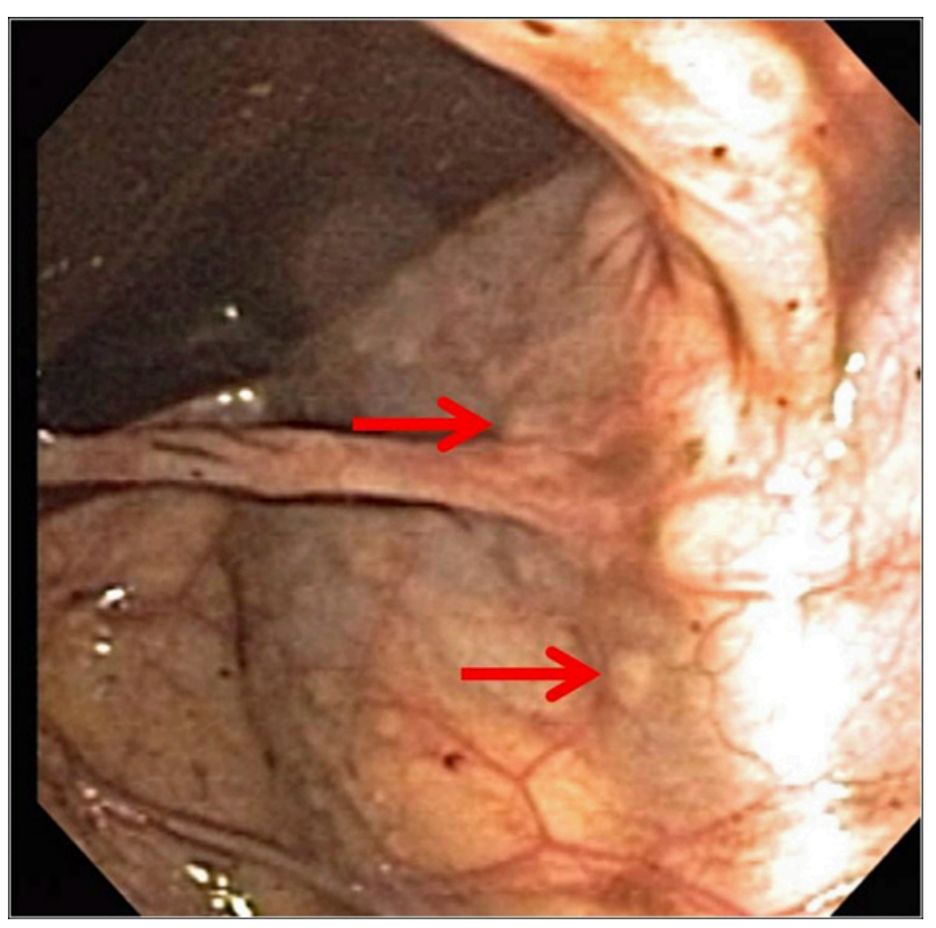

由于直肠出血、心动过速、轻度贫血等原因,留院观察。在接下来的24小时内,排一次无痛的黑便,血红蛋白水平下降了20 g/l至85 g/l(平均红细胞体积,89.4 mm3;红细胞分布宽度,13.7)。进一步的实验室检查显示网织红细胞计数为1.2%,国际标准化比率为1.1,部分凝血活酶时间为38.1s,血管性血友病检查阴性。患者的白蛋白、红细胞沉降率和尿分析结果均正常。随后的内镜检查和结肠镜检查显示直肠扁平。图1示结肠淋巴组织增生(箭头所示)。